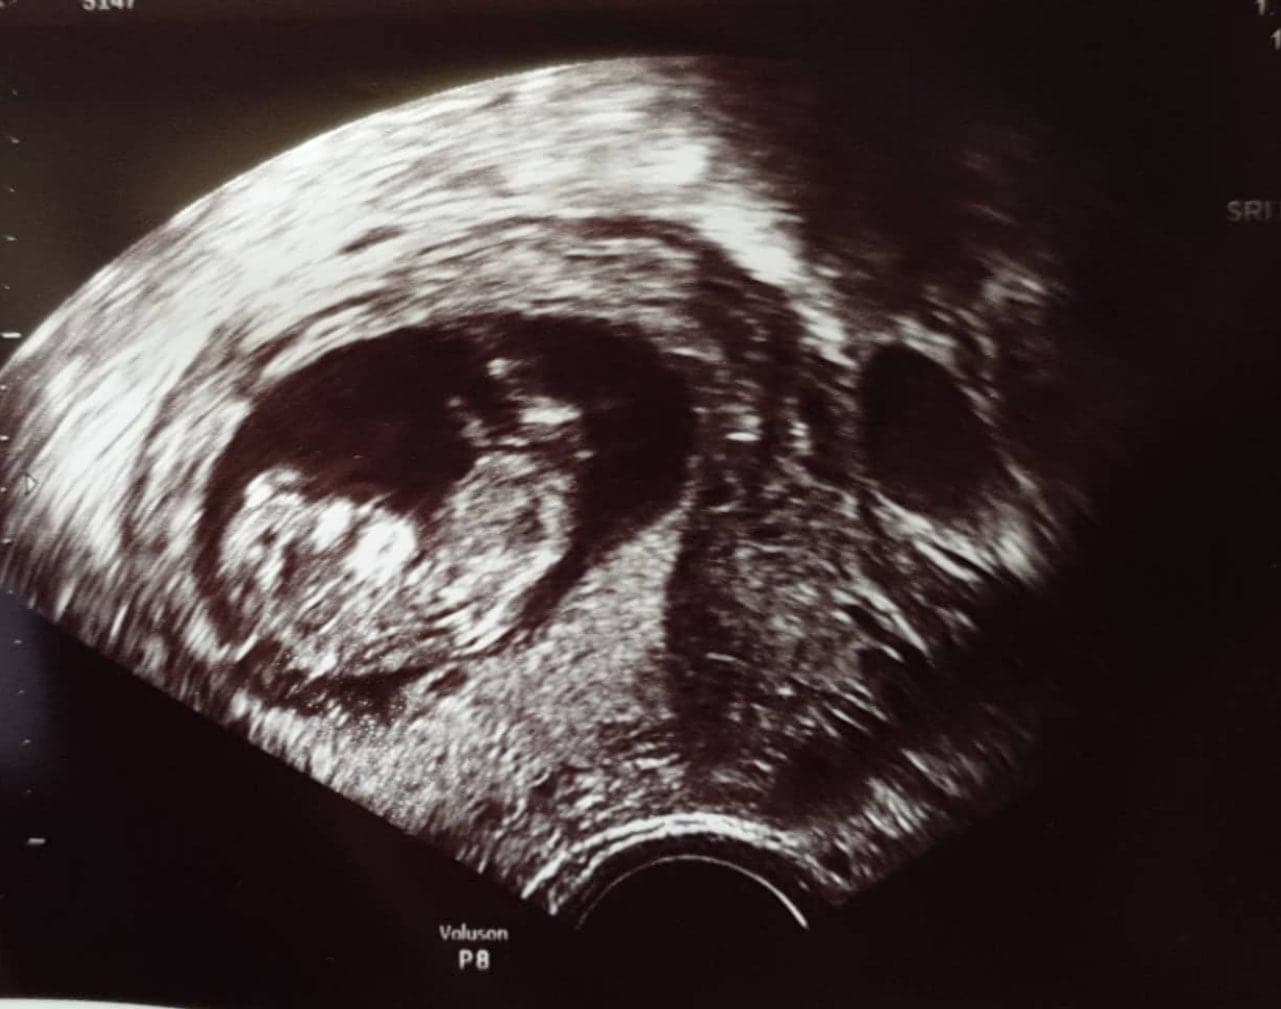

Ultraschallbilder aus dem 2. Trimester (13. bis 28. SSW)

Im 2. Trimester bekommt man oft die schönsten „Ganz-Körper“ Ultraschallbilder. Das Baby ist nun so groß, dass man alles gut erkennen kann und noch nicht zu groß, so dass es noch ganz auf das Bild passt. In dieser Zeit lässt sich meist das Geschlecht bestimmen, wobei manche Babys es einfach nicht preis geben wollen und sich immer so drehen, dass man nichts erkennen kann.